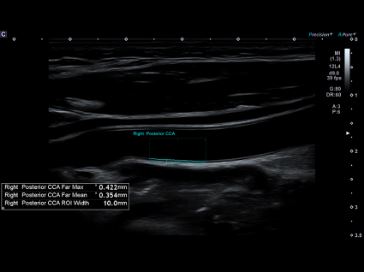

Автоматичне вимірювання комплексу інтима-медіа Auto IMT допомагає підвищити як точність, так і швидкість допплерівських досліджень сонної артерії.